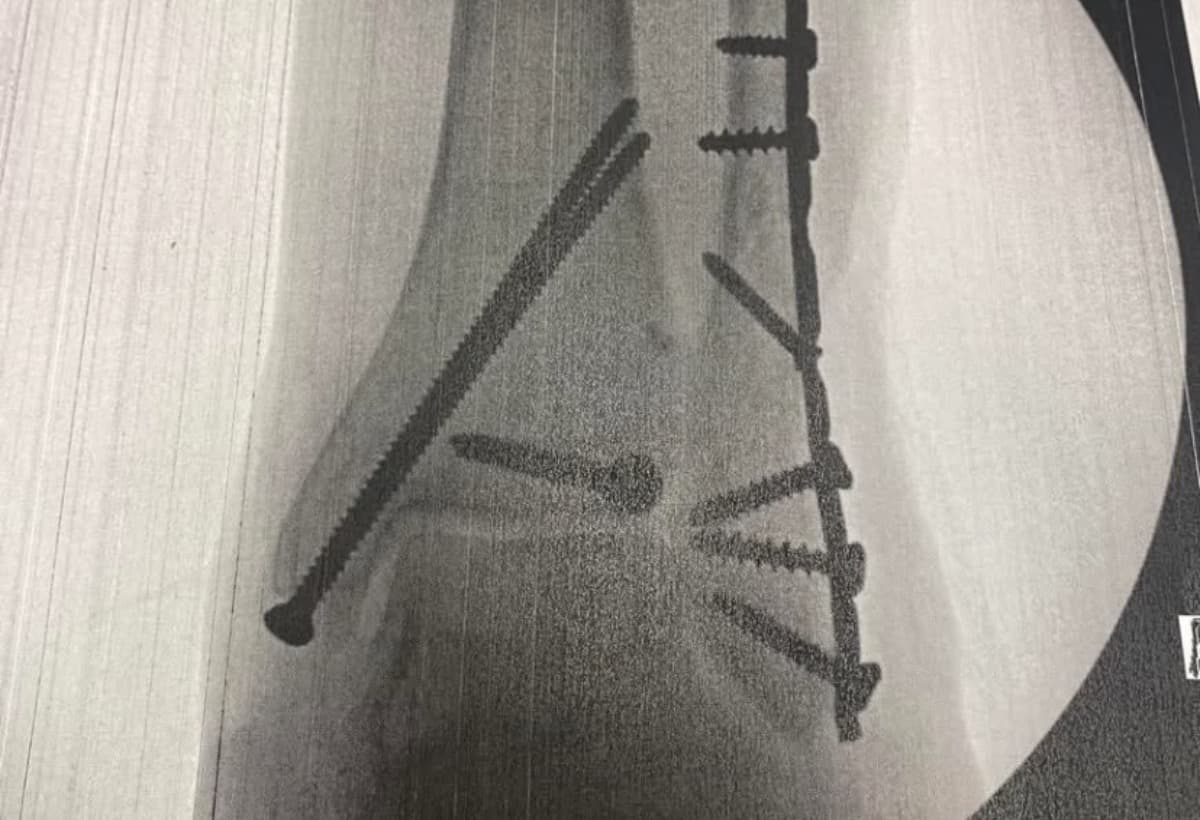

I had surgery the next morning-8 screws, two pins, and a plate. That was the easy part. The weeks after proved challenging-to say the least. I felt helpless, with only my son to help me, The pain seemed relentless. And I lost 100 percent of my independence.

The break is called trimalleolar fracture with dislocation and is in the top 7 percent of the most serious injuries one can have with an

ankle.